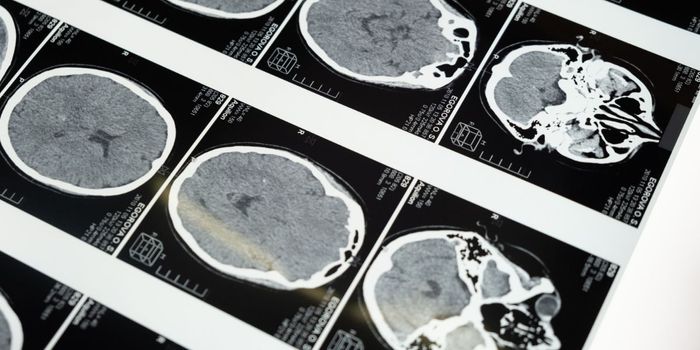

MAR 30, 2016Health & MedicineResearchers claim to have pinpointed the neural stem cells that Zika seems to be targeting. The Zika virus outbrea ...

NOV 04, 2020Health & MedicineCOVID-19, the illness caused by the pandemic virus SARS-CoV-2, is known to cause blood clots all over the body in some p ...

OCT 05, 2020MicrobiologyPediatric hydrocephalus - excessive fluid on the brain of a child - has been connected to a bacterial pathogen.